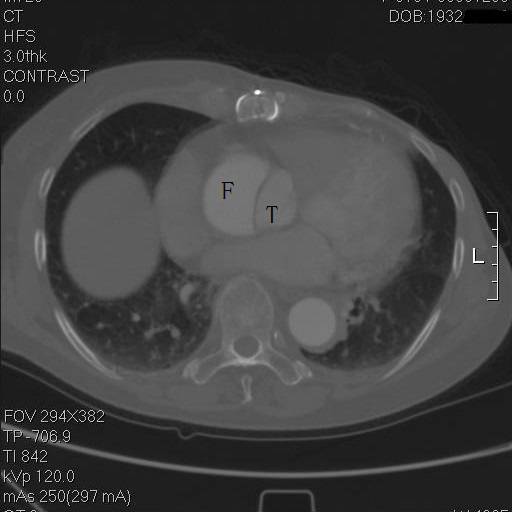

患者是一例A型主动脉夹层,上图中F示假腔,T示真腔,这没什么奇怪。但仔细一看,胸骨的边缘具有高密度影,中间还有一小片低密度区,这例病例接受过前胸正中开胸的手术。

是的,回顾其病史,她一年半前,罹患A型主动脉夹层,第一内膜破裂口在右冠上方,夹层延续到弓部,在弓上分支开口处撕裂形成了出口,她接受了一种显得有些奇怪的术式。

往上阅片,假腔内竟然有一个支架影!

再往上,这个支架竟然是骑跨在真假腔之间的!

这个层面,支架终于完全在真腔内了,但假腔基本没有闭合。

到弓部可以看到,支架远端贴得倒还可以

冠状面重建,方框示头臂干看上去完全开口于假腔,左颈总似乎被支架盖住了